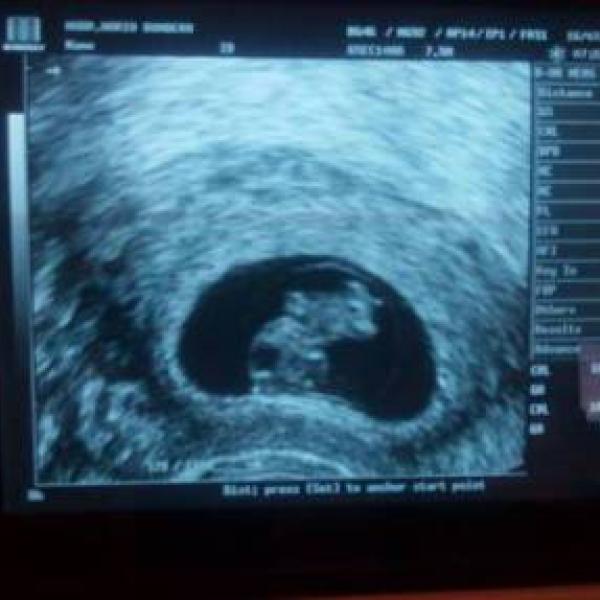

Moc mila dr mi udelala utz a konstatovala ze vidi gestacni vacek prumer 15mm, pritomen zloutkovy vacek, embryonalni struktury zatim nezobrazuji. Zaver 7tt(6+4) dle posledni ms,AB imminens - cituji ze zpravy.